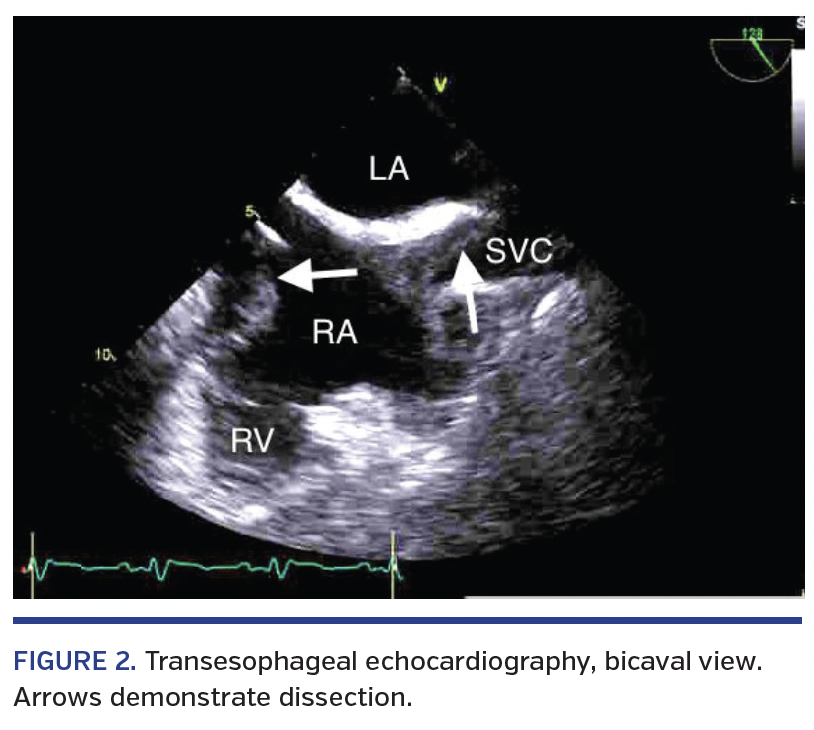

A 62-year-old male with an abnormal stress test underwent stent placement of the left anterior descending coronary artery. Soon after, this was complicated by stent thrombosis leading to cardiogenic shock that was refractory to pressors, requiring intra-aortic balloon placement. The patient was eventually weaned off pressors and ventilatory support, but developed septic shock secondary to hospital-acquired pneumonia, and shortly thereafter developed cardiogenic shock. A Swan-Ganz catheter was then placed with the aide of an Arrow Spring-Wire guide (Teleflex), marked 0.035˝ diameter x 17-3/4˝ with an Arrow Advancer (Teleflex). The patient remained hemodynamically stable throughout the procedure. Transesophageal echocardiography was then performed after placement to rule out any cardiogenic abnormalities contributing to the presentation. Results demonstrated a right atrial dissection with extension into the superior vena cava and right ventricle not seen on previous echocardiographic findings (Figures 1 and 2). No intervention was performed as the patient’s hemodynamic status improved. We propose that during Swan-Ganz catheter placement, the guidewire sheared the intimal lining of the superior vena cava and endocardium.